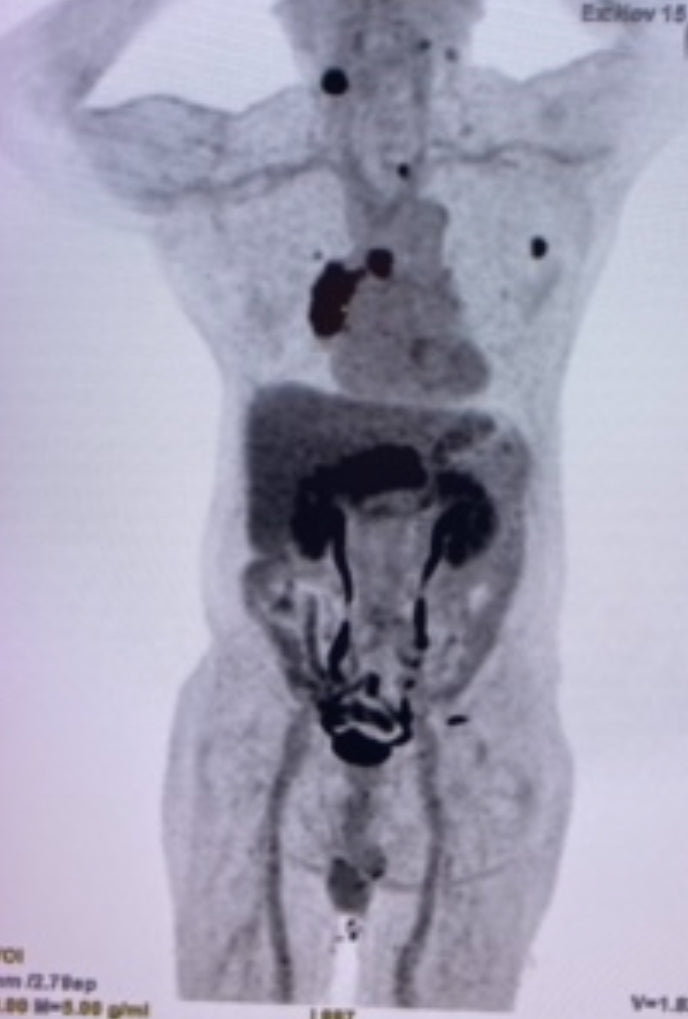

作為一個放射科專科醫生,很多時候是在黑房裏埋頭苦幹的研究形像,包括不同癌症的電腦掃描,磁力共振,正電子掃描,乳房造影,超聲波,也會動動手做抽針(抽取組織化驗)。無論是做癌症篩查,第一個診斷出癌症,或是運用影像評定癌症擴散情況,或是癌症治療後的定期影像follow up,通常我們都是在後排默默耕耘,寫了一疊又一疊的報告。今次,趁這個機會,從後排跳到前方,身體力行代表「癌症資訊網」跑步,希望讓你們知道,你們有我的支持,你的積極,使我要更進步,𢹂手對抗癌症。